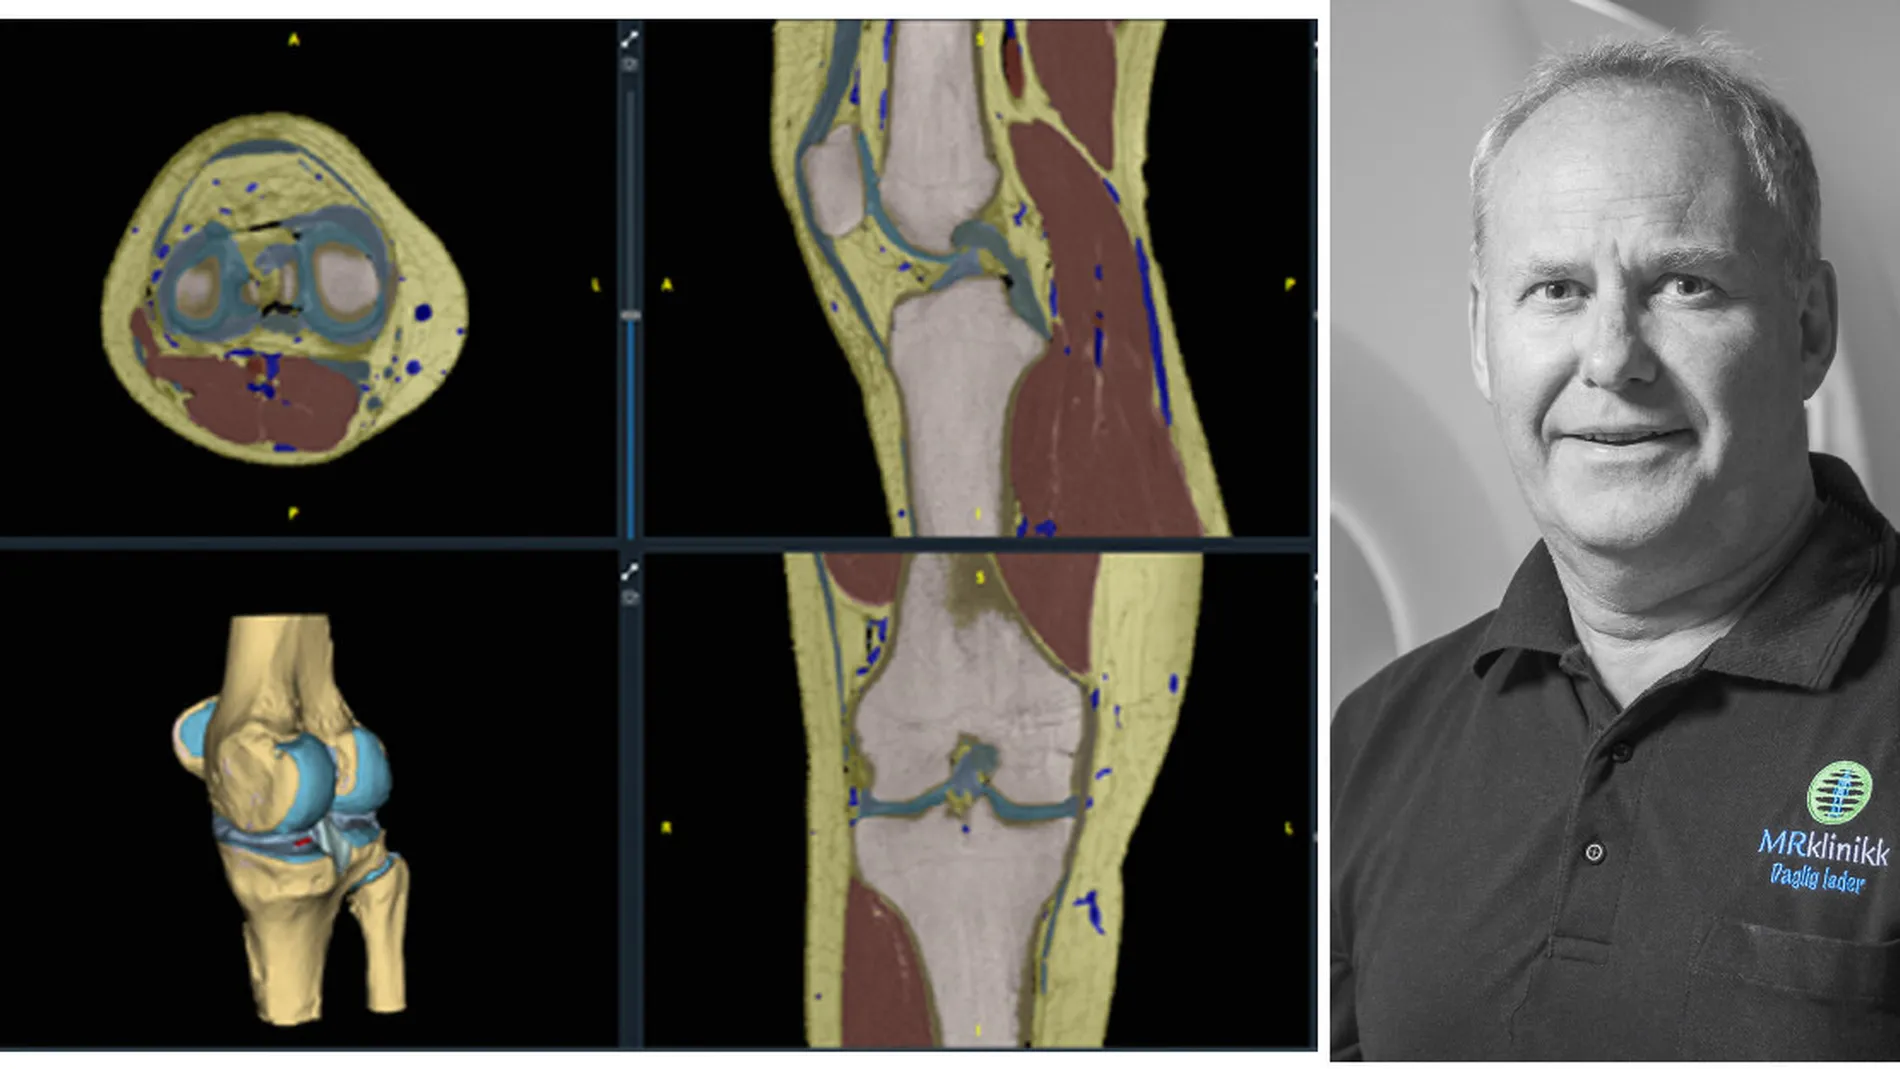

Formålet med programvaren er å automatisk finne knestrukturer i pasienter fra høyoppløselige MR bilder. Den bruker den nyeste teknologi innen kunstig intelligens for å lære seg å kjenne igjen strukturer som ben, muskler, sener, leddbånd og blodårer.

Denne informasjonen brukes til å gjenskape detaljerte 3D-modeller av pasientens kne - som leger i framtida kan bruke til å planlegge og gjennomføre kneoperasjoner.

– Det dreier seg om å avbilde anatomien så nøyaktig som mulig og lære datamaskinen hva den ser på bildene. Det er et voldsomt gjennombrudd regnemessig. Resultatet som det ville tatt en lege flere dager å mate inn manuelt, er nå klart på ett minutt, forteller Gjesdal.